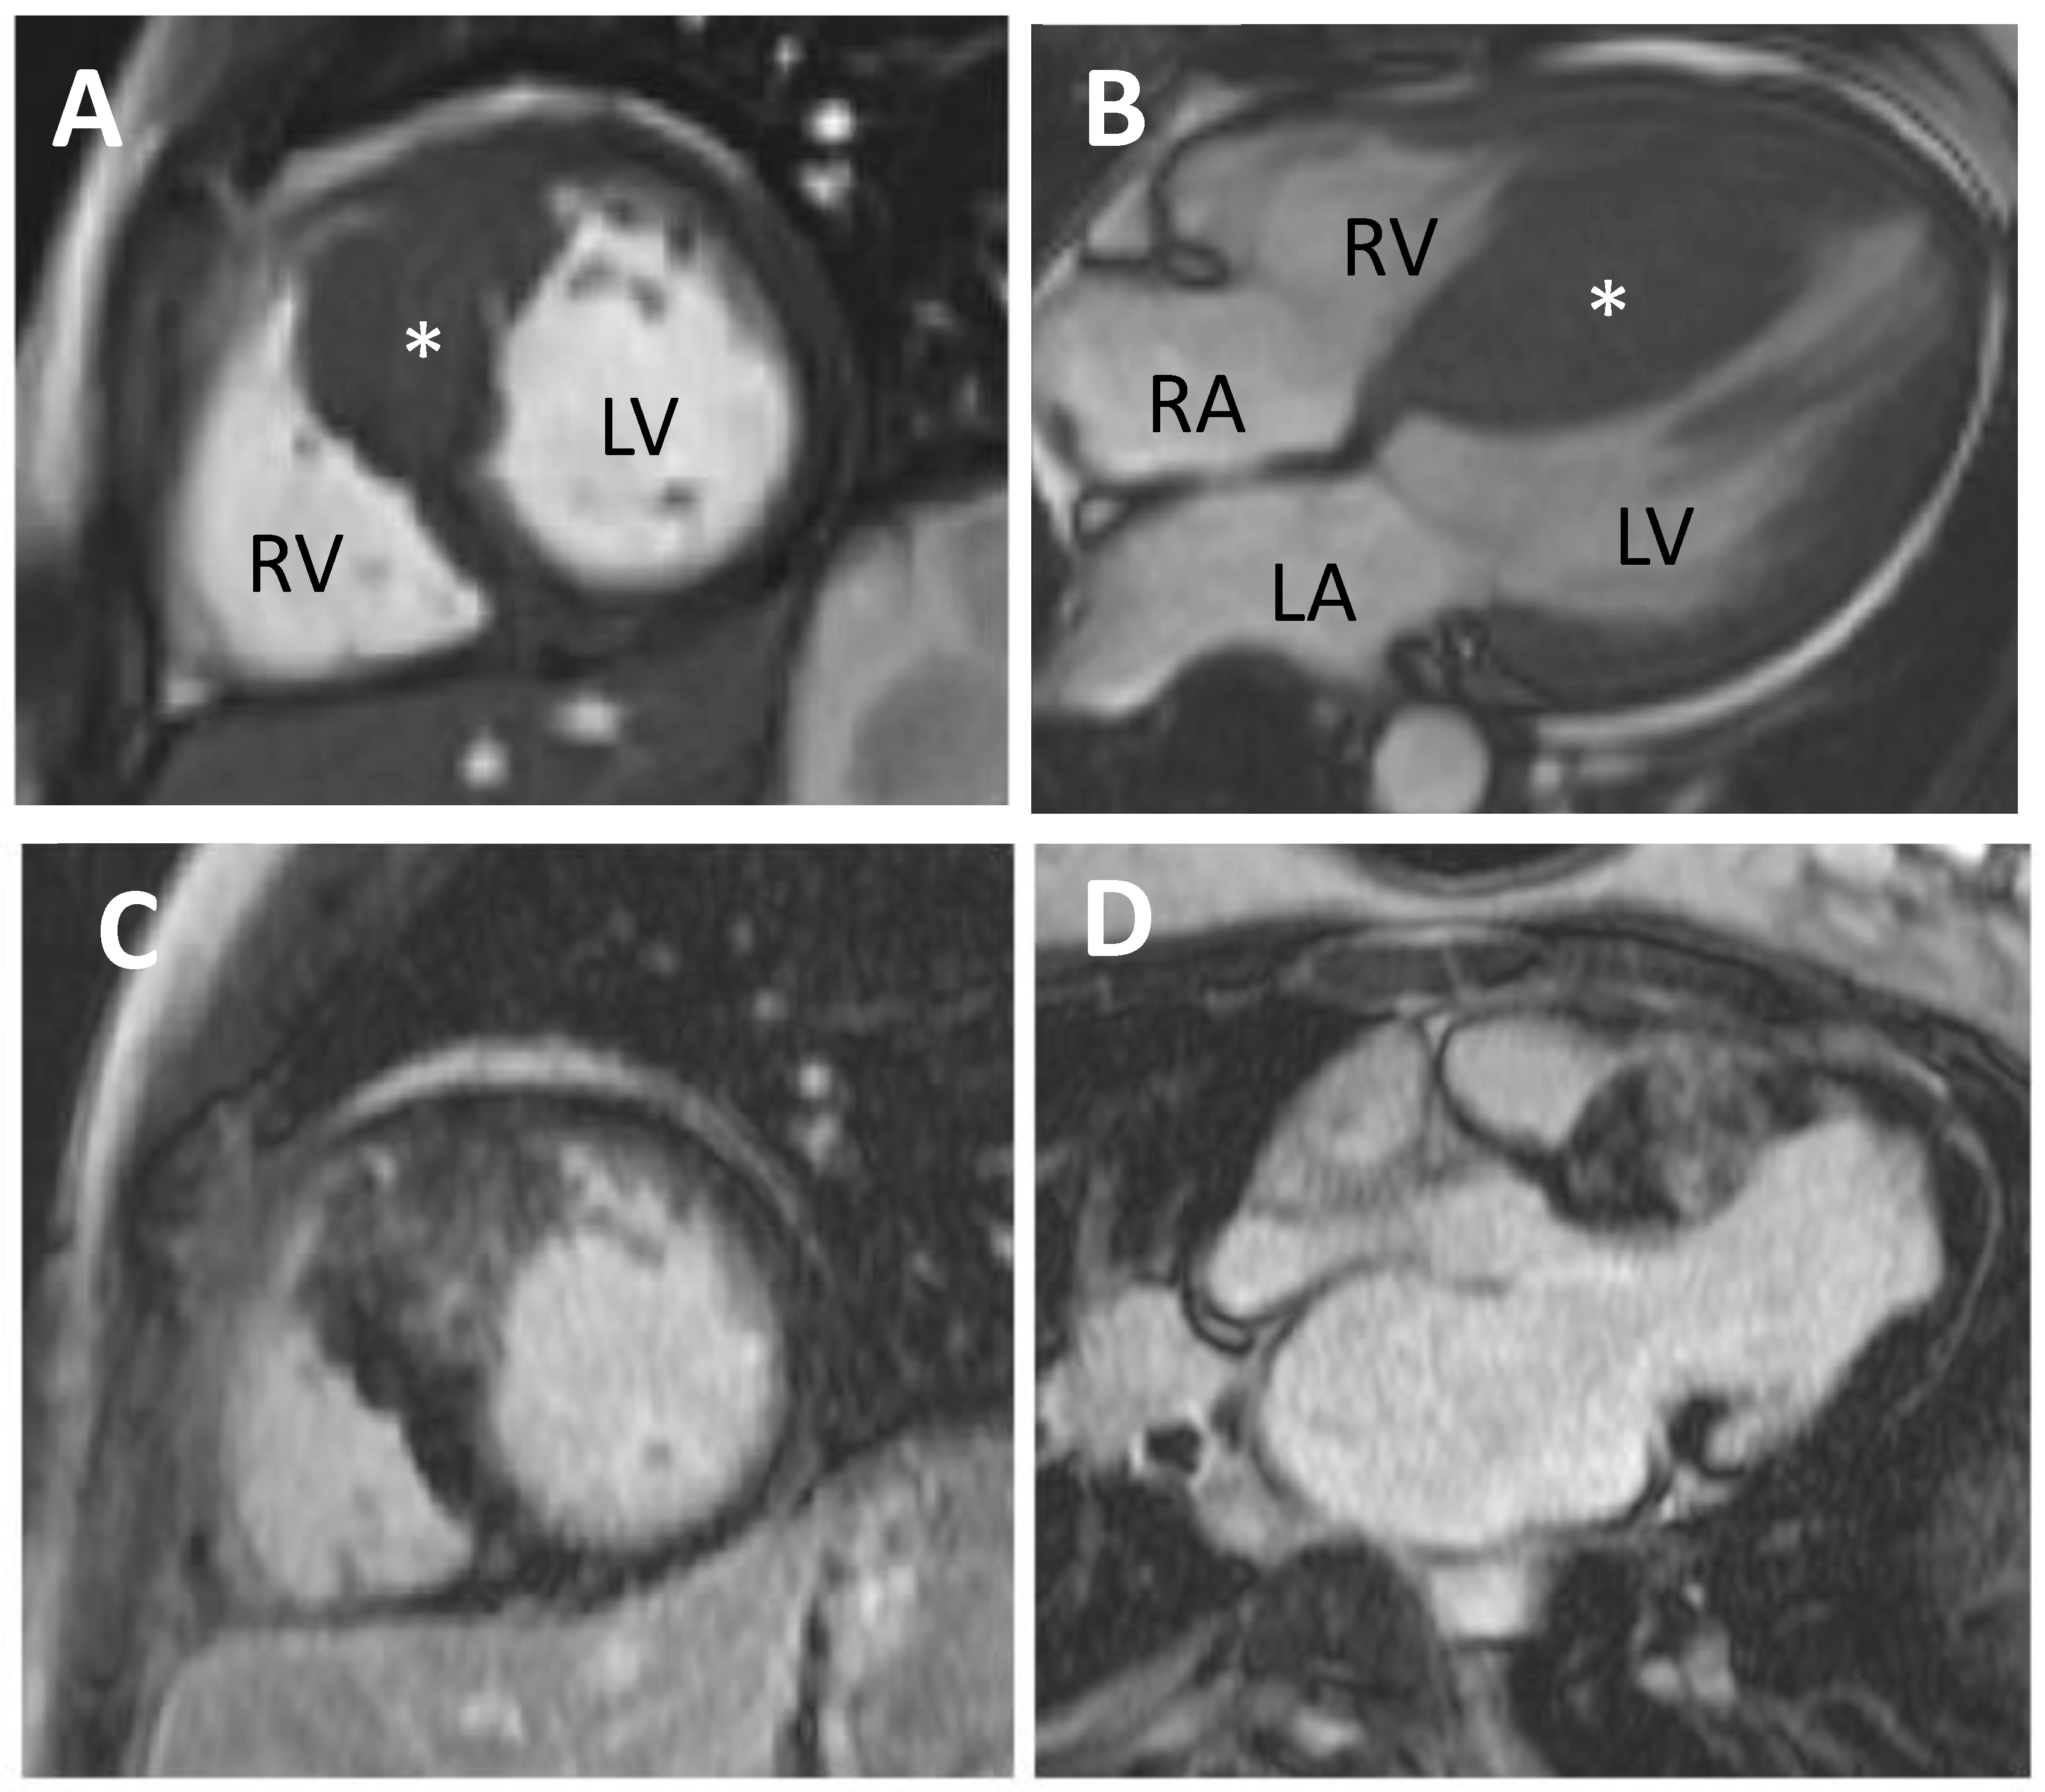

5.1. Cardiovascular Magnetic Resonance (CMR)

11.1. Diagnosis

11.1.1. CMR